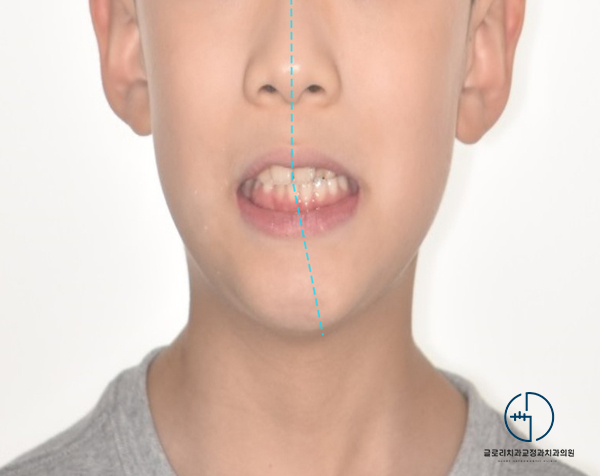

처음 환자의 얼굴을 마주했을 때

딱 느낄 수 있었는데요.

실제로 안모 사진을 확인해 보면

좌, 우 가 뒤틀려 있는 것이 관찰되었습니다.

치열에는 문제가 없는지 살펴봐야겠죠?

왼쪽 두 번째 앞니에서

반대교합(crossbite)이 나타나고 있었는데요.

이곳이 거꾸로 물리면서

턱을 왼쪽으로 비틀어 물고 있는 상태였습니다.

자세히 살펴보니 문제는

두 번째 앞니에만 있는 게 아니었는데요.

전체적으로 반대교합이 나타나 있었으며

위아래 중심선이 맞지 않고

안모 비대칭까지 나타나 있는 상황이었습니다.

좌우 불균형이 나타났던 이전과는 달리

양쪽의 균형이 잘 맞고 있는 것이 관찰되었습니다.